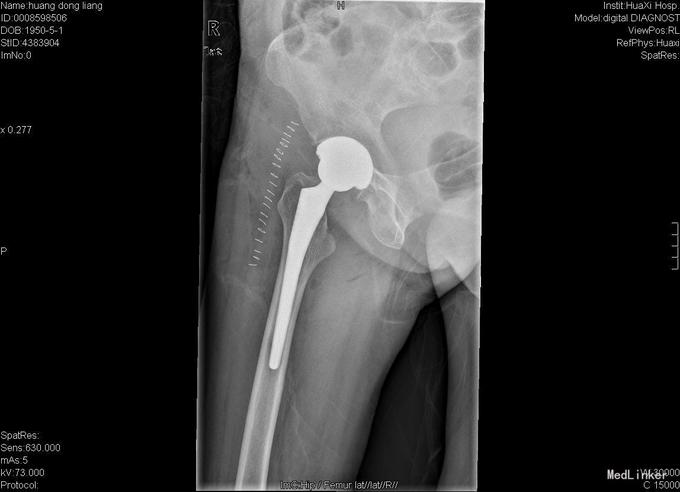

患者女,70岁,因"摔伤后右髋部疼痛、活动障碍10小时"入院,患者诉10小时前在家不慎滑倒,当即感觉右髋部疼痛、活动障碍,于当地医院急诊检查示:右股骨颈骨折,为求进一步诊疗故来我院。

查体:右髋部略水肿,右髋关节活动受限,不能负重。右髋部压痛(+),纵向叩击痛(+)。右髋关节活动受限,右膝及踝、足趾诸关节活动正常。 辅查:X线片示右股骨颈骨折,断端分离、错位。

入院诊断:右股骨颈骨折 诊疗计划:择期手术治疗,行右侧全髋关节置换。